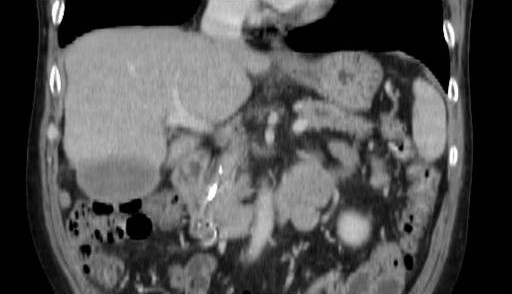

A 57-year-old man with a one year history of alcohol-induced chronic pancreatitis presented with a 1-month history of intermittent epigastric pain. He denied any associated nausea, vomiting, diarrhea, weight loss or other gastrointestinal symptoms. His past medical history was significant for hypertension, type 2 diabetes mellitus, dyslipidemia and chronic obstructive pulmonary disease. The abdomen was soft and non-tender. The liver and spleen were not felt, and no abdominal mass was appreciated. His physical examination was otherwise unremarkable. Laboratory evaluation revealed serum amylase of 356 U/L (reference range: 30-111 U/L) and a lipase of 679 U/L (reference range: 46-218 U/L). Complete blood counts, liver chemistries, carbohydrate antigen 19-9, and alpha-feto protein levels were all normal. Pancreas protocol CT scan of the abdomen revealed a 8x5 cm cystic fluid collection in the left liver lobe, an L-shaped subcapsular fluid collection inferior to right hepatic lobe 10x9 cm in size and a 2.4 cm complex fluid accumulation that involved the head and the superior aspect of the body of pancreas (Figure 1). CT guided diagnostic aspiration of the hepatic cystic lesion drained 100 mL of straw-colored fluid which showed no organisms on gram stain and was sterile on bacterial and fungal cultures. Cytological examination of the fluid did not reveal any malignant cells. The amylase level in this fluid was greater than 51,065 U/L which confirmed the diagnosis of intrahepatic pancreatic pseudocyst extension. At the time of CT guided aspiration, the pseudocyst was treated with percutaneous drainage with the placement of an 8F pig-tail catheter. The intrahepatic pancreatic pseudocyst extension failed to resolve even after 4 weeks of the pig-tail catheter placement (Figure 2). At this point, an ERCP was performed which revealed a normal cholangiogram. Pancreatography revealed a normal-appearing main pancreatic duct to the region of the pancreatic neck, and a ductal stenosis 12 mm in length was identified beginning at the pancreatic body near the neck. The main pancreatic duct and pancreatic duct branches were dilated upstream of the stenosis to about 7 mm (Figure 3). After performing an 8 mm ventral pancreatic sphincterotomy; the stricture was dilated with a 6 mm biliary dilating balloon and a 7F, 10 cm long pancreatic stent was inserted to the tail (Figure 4). Brush cytology and intraductal biopsy specimens were obtained from the stricture and revealed fibrosis and changes of chronic pancreatitis; they were negative for malignancy. EUS examination revealed a pancreatic head cystic lesion extending into the left hepatic lobe (Figure 5ab); fluid examination revealed an amylase of 54,450 U/L and the cytology was negative for malignancy. A follow-up pancreas protocol CT of the abdomen 6 weeks later revealed complete resolution of the pancreatic head fluid accumulation and the intrahepatic pancreatic pseudocyst and decrease in size of the L-shaped subcapsular fluid collection to 2x4 cm (Figure 6). Percutaneous drainage of the remaining L-shaped subcapsular fluid collection was discussed with the patient but he refused any percutaneous or surgical drainage. A follow-up pancreatogram revealed marked improvement in the pancreatic duct stricture. He remains asymptomatic after 9 months of follow-up.

Figure 6. Repeat CT scan at 10 weeks showing complete resolution of the intrahepatic pancreatic pseudocyst with improvement of the subcapsular fluid collection. |